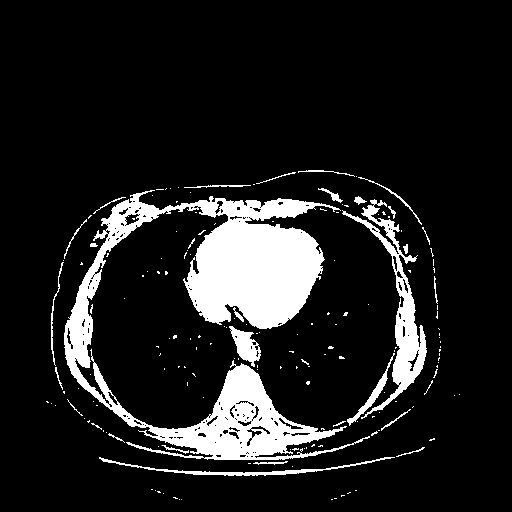

Original NATIVE CT scan (input)

Full window (WL 1023.5, WW 4095 β†’ Low βˆ’1024, High +3071)

Actual HU range: [-1024.0, 3071.0]